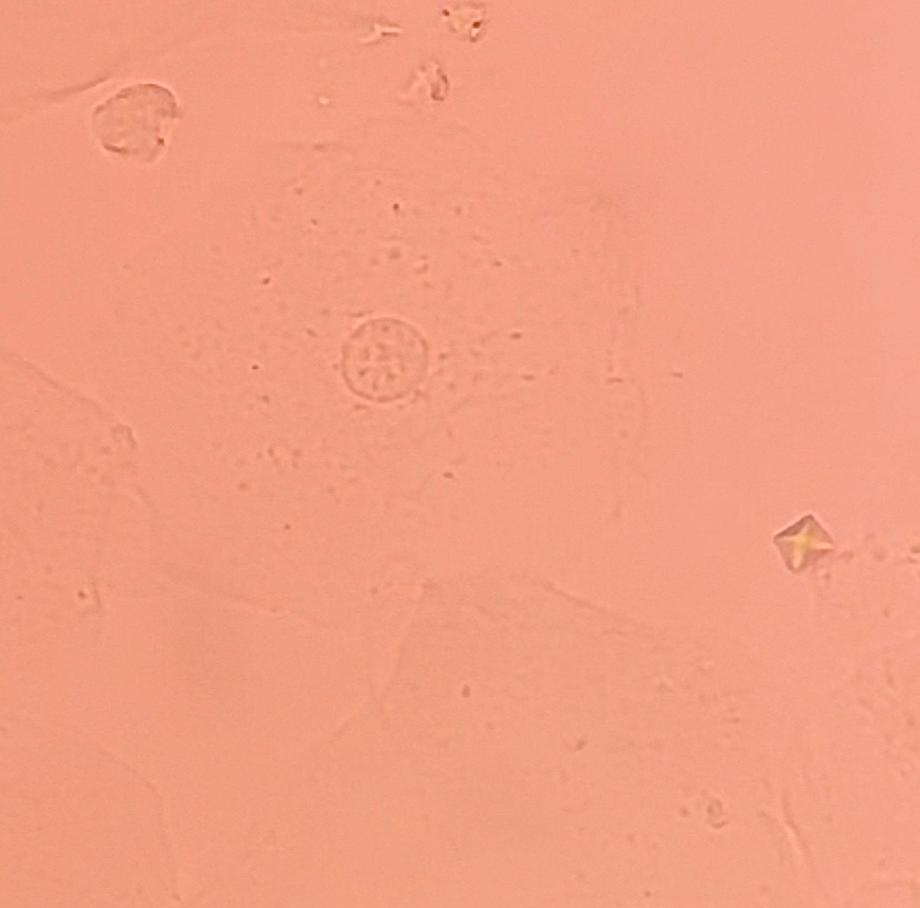

본문 시작 요 pH 측정 임상병리학과 404 2025-05-19 요 pH를 측정해본 후 산성뇨, 염기성뇨와 관련된 질병에 대해 알아보는 시간을 가졌습니다 목록 이전요시험지 테스트 다음 환자 검체를 이용한 요침사 검경 & 회식 만족도조사 만족도 조사 이 페이지에서 제공하는 정보에 대하여 만족하시나요? 매우만족 만족 보통 불만족 매우불만족